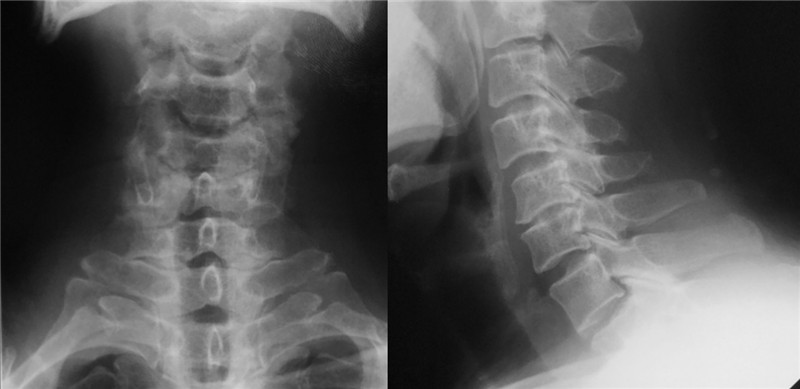

术前X线

颈椎斜位X光片有助于观察钩椎关节

诊断:

混合型颈椎病

颈椎管狭窄症